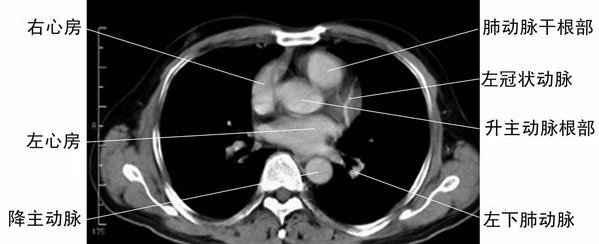

左心房层面-胸部CT断层影像